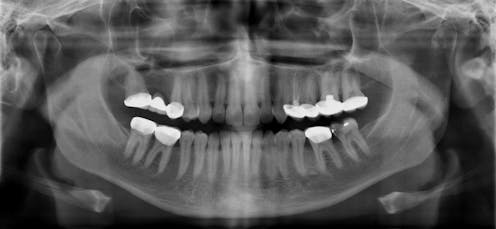

A team at the Tygerberg Oral Health Centre at the University of the Western Cape’s faculty of dentistry traced how tik affects users’ teeth and gums. Tik causes serious mouth and teeth problems commonly known as “meth mouth” – that presents as extensive tooth decay and gum disease. Once the damage begins, it is virtually impossible to stop and in many cases leads to multiple tooth extractions. Based on our findings we recommend early diagnosis to prevent the rapid and extensive deterioration.

My colleagues and I at the Tygerberg Oral Health Centre noticed an increase in the number of young adult patients presenting with multiple badly decayed teeth. We saw an unusual pattern of tooth decay. These patients presented with cavities on the smooth surfaces of the teeth, leading eventually to total destruction of the tooth.

To exacerbate matters, tik users often grind their teeth because of drug-induced hyperactivity, anxiety and nervousness. This causes accelerated tooth wear. Furthermore, they lose interest in basic personal and dental hygiene. A tik “high” can last for days; users don’t bother brushing their teeth for extended periods causing plaque to accumulate and the bacteria to continue metabolising sugars into acids. The acidic environment often leads to erosion and when mouth pH drops below critical levels, tooth decay is the result.

Dentists should be trained to identify users presenting in their clinics, as should other health care workers (nurses, doctors, community health workers) and addiction specialists who need to be aware of oral health problems among tik users. Combating the public health problem and social nightmare of tik abuse requires buy-in from government, industry and society. And perhaps seeing images of a “meth mouth” might go some way in putting anyone off drug use for life.